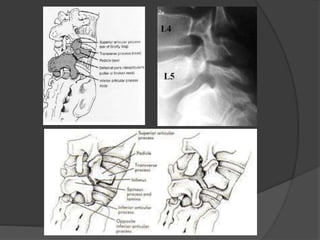

Espondilolisis  Consiste enla rotura de la lámina de la vértebra, de forma que la articulación facetaría queda separada del resto. La vértebra que se afecta más frecuentemente es la quinta lumbar, seguida por la cuarta.

 Rx perfil se aprecia el desplazamiento de la L5

 las proyecciones oblicuas se pone al

descubierto la falta, de sustancia ósea a nivel